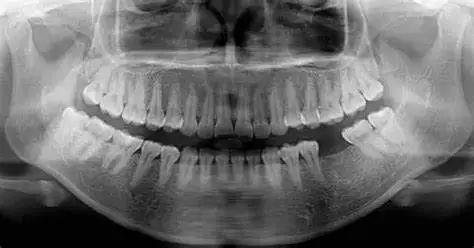

X光顯示,堅(jiān)持叩齒者牙槽骨密度比不練習(xí)者高19%,牙周膜彈性提升37%。

每年拍全景牙片(檢測(cè)智齒阻生風(fēng)險(xiǎn))